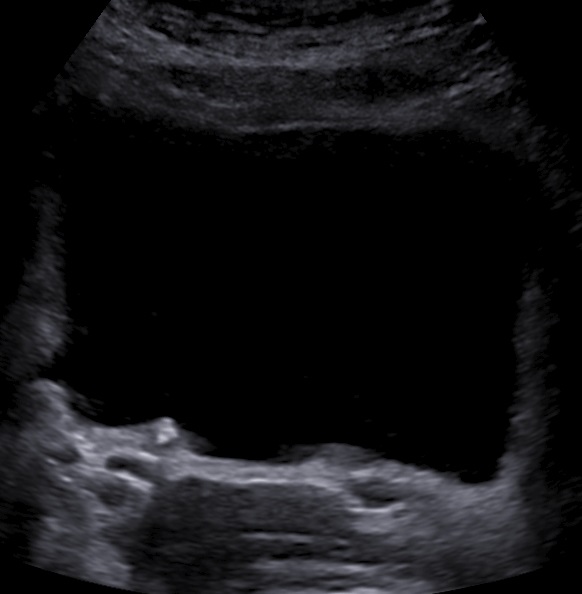

Even abdominal sonography could demonstrate the small ureteral stone.

A tiny blood clot could be seen inside the bladder.